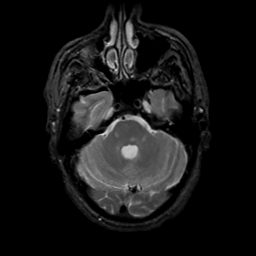

MR Study #13, May 19, 1991 -- Slice #13